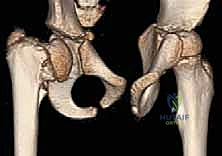

في حالة الفحج الرضخي النمائي، يحدث خلل في تعظم صفيحة النمو لعنق الفخذ. تصبح هذه الصفيحة أوسع من المعتاد، وتتخذ وضعاً عمودياً غير طبيعي. والأكثر تميزاً هو ظهور نمط يشبه حرف (Y) المقلوب على الأشعة، وذلك بسبب وجود قطعة عظمية مثلثة الشكل (Triangular metaphyseal fragment) في الجزء السفلي من عنق الفخذ. هذا الخلل يضعف العنق ويجعله عرضة للانحناء تحت وزن الجسم.

3. البحث عن العلامة المميزة: الشظية العظمية المثلثية (Triangular fragment) في الجزء السفلي من عنق الفخذ، والتي تعطي صفيحة النمو شكل حرف Y المقلوب.

في بعض الحالات المعقدة، أو للتخطيط الجراحي الدقيق، قد يطلب الدكتور هطيف إجراء تصوير بالرنين المغناطيسي (MRI) أو تصوير مقطعي محوسب (CT Scan) ثلاثي الأبعاد لتقييم الغضاريف المفصلية والتروية الدموية بدقة متناهية قبل المشرط الجراحي.